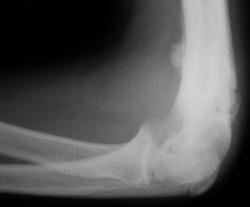

Травма 2 недели тому. Пациент за медицинской помощью не обращался. В ЛПУ "приведен женой". После осмотра  хирургом направлен для рентгенографии локтевого сустава. Выполнить рентгенографию в стандартных проекциях невозможно.

Не патологический ли это перелом? Мне кажется имеет место остеомиелит по заднему контуру дистального эпифиза плечевой кости секвестрация. Непонятное ощущение того что плечевая кость повернута по своей оси???А что за остеофит на переднем контуре плечевой кости?

Возможно, это не первая травма. За медицинской помощью-то пациент обращаться не любит. А рука красная, утолщенная, горячая?

А еще и линейный периостит в области плечевой кости?

Ну, не знаю.....и линейный периостит, и "остеофит" по передней поверхности укладываются в костную мозоль.

17 лет.